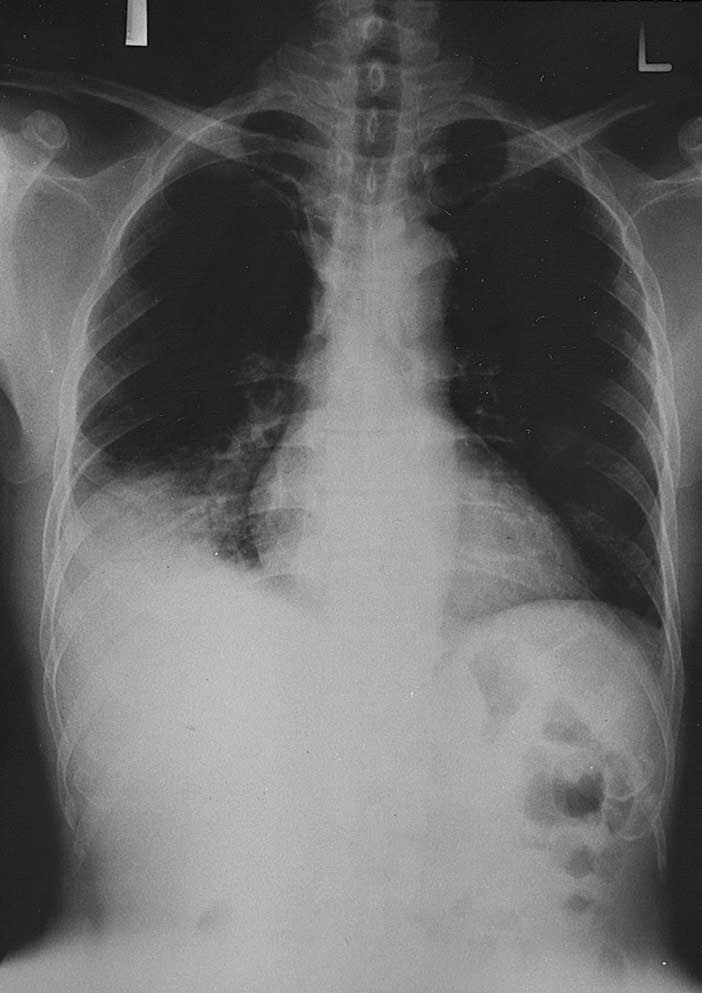

Figure 1. Patient¡¯s chest Xray on admission Mycoplasma Pneumoniae Chest X Ray Following Pneumonia Your baby or young child has pneumonia; Learn about the symptoms, diagnosis and treatment of pneumonia in adults, a type of chest infection. Who are at higher risk of underlying malignancy. It includes recommendations on chest. In hospital you'll usually be given fluids and antibiotics to treat the infection. Find out when to investigate. Diagnosis based on symptoms and signs. Chest X Ray Following Pneumonia.